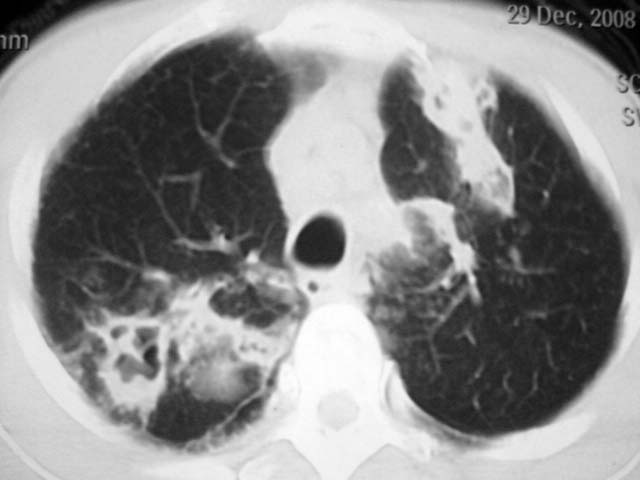

男,52岁,发热2月,糖尿病史。

抗结核治疗irpz方案,血糖未治疗,空腹15.9左右。症状无好转,左胸痛。

2、双肺见多发片状及结节状高密度影,大多数病灶中心均见“空泡征”。

3、纵隔内淋巴结肿大。

结果:两肺继发性肺结核并曲霉菌感染。